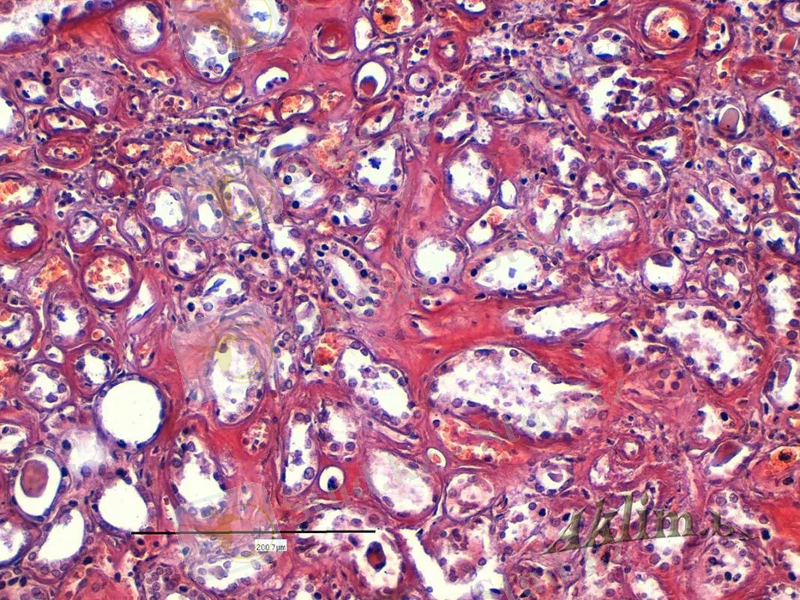

Гломерулонефроздар негізгі өзгерістердің бүйрек шумақтарында туындаумен сипатталады. Олардың бірі- шумақ тамырларының гиалинозы. Альбуминдер мен глобулиндер есебінен қабырғасы қалыңдаған, қуысы тарылған шумақ қылтамырлары эозинмен солғын қызыл боялады, жарық микроскопыымен тартпалар мен сақиналар түрлерінде көрінеді. Көлемі әжептеуір гиалин цилиндірлер пайда болады. Жай көзбен бүйректің қуқылданғаны, зақымданған шумақтар ақшыл жылтыр немесе көмескі нүктелер түрінде байқалады. Процесс ұзағыра өткен жағдайда мүше бүрісіп, беті аздап бұдырмақтану мүмкін консистенциясы нығызданады.

Амилоидтық нефроз. Бүйрек шумақтарында күрделі зат - амилоидтың шөгіп, қылтамырлар қабырғаларының қалыңдауы. Зақымдану деңгеці тым зілді болған жағдайда тамырлар ілмектері сүртіліп ктееді. .